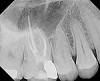

Fig. 11 All four canals were obturated with BioCeramic Sealer and BC Coated gutta-percha cones.

Figure 11

Fig. 12 The original ultra-conservative access may have saved some tooth structure, but would have resulted in missing the MB2, which would have negatively affected the case outcome postoperatively due to its separate apical exit.

Figure 12